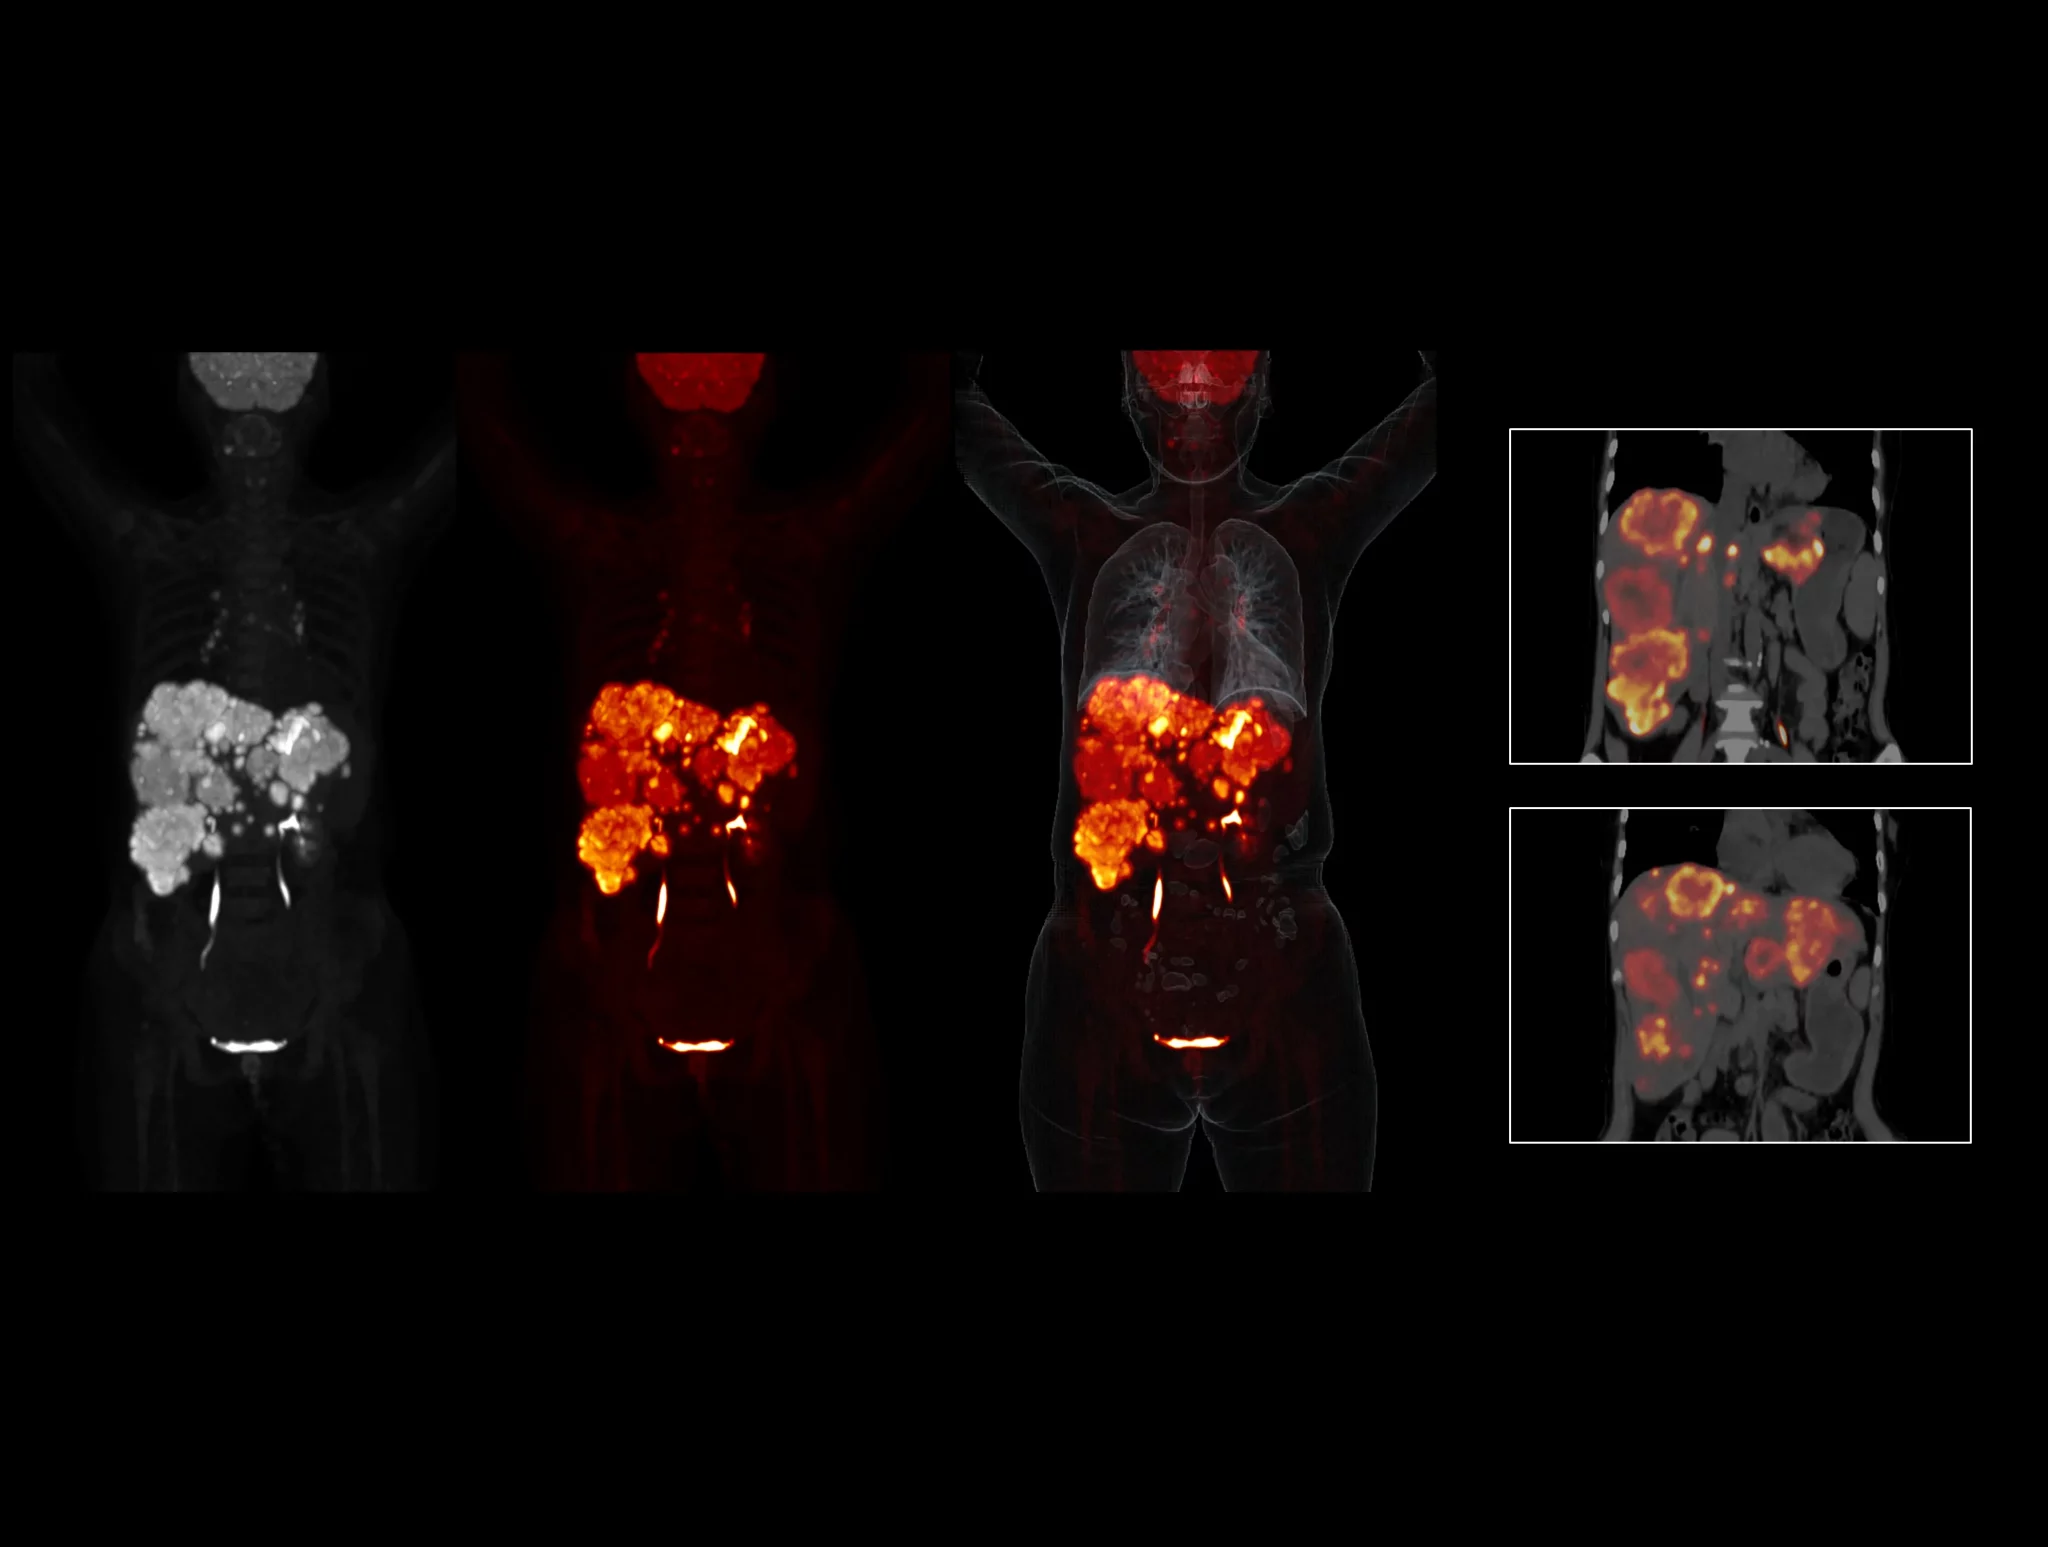

With the ultra-high system performance, uMI Panorama faces up to the challenges of tracers with different half lives and the complex scanning conditions, without compromise for image quality.

New-Tracer Imaging

Click on different tracers to see the images.